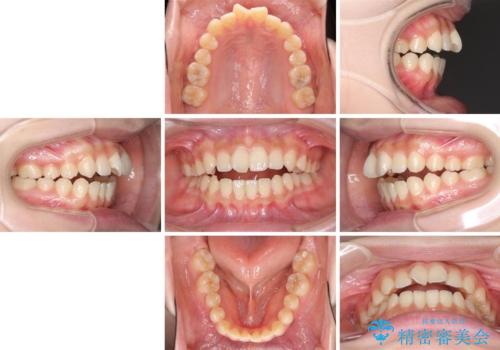

話しにくいオープンバイト ワイヤー装置による抜歯矯正治療

- 前歯のオープンバイトを気にして来院された患者様です。

上下前歯の前後位置が大きくずれていたため、上顎左右第一小臼歯2本を抜歯してワイヤー装置による矯正治療を行うこととしました。

オープンバイトの原因は舌の突出癖であり、癖が改善されないと治療経過に影響を及ぼすため、舌のトレーニングを指示しました。

なかなか癖が改善されず、トレーニングも断続的に行ったため、治療期間は長期化しました。